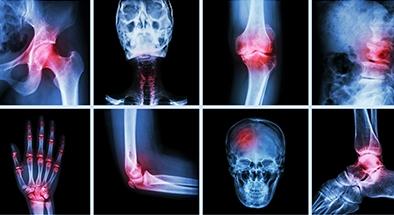

Joint Replacement

When total joint replacement is necessary, our expert staff of orthopedic surgeons, nurses, physical therapists, occupational therapists and support staff are here to make sure you receive the high quality, award-winning and compassionate care that we have offered our South Florida community since 1955!